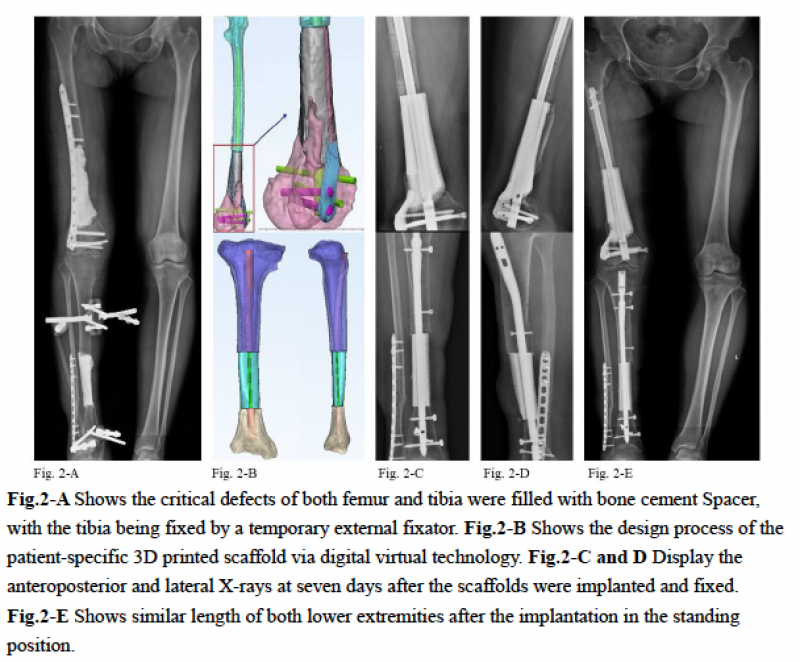

一期:彻底行瘢痕组织及硬化骨切除,在缺损区填充骨水泥Spacer,留置引流。术后拔除引流管后对双下肢进行三维CT扫描,通过医工结合进行3D打印假体设计及制备。

二期:8周后取出缺损区骨水泥Spacer,植入个性化设计的3D打印微孔钛合金假体,并分别进行股骨拟行髓内钉及胫骨髓内钉固定。

随访:术后复查X光片见右侧股骨、胫骨的对位、对线及下肢力线满意,骨缺损区匹配良好。术后26月仍见局部稳定,未见假体下沉及内固定松动,局部骨痂生长满意,同时患者膝、踝关节功能良好。

图2: 3D打印假体的设计及术后X光片